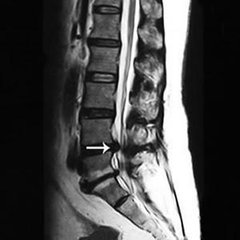

腰椎间盘脱出是什么?腰椎间盘脱出属于腰椎间盘突出症中的一个疾病发展阶段,并且脱出属于腰椎间盘突出症中较严重阶段,椎间盘内的髓核突破纤维环,进入椎管,对神经造成严重压迫,但尚未有效从纤维环中脱离。没有髓核做支撑,相邻脊椎骨长时间摩擦还会导致骨质增生病症即骨刺。因此腰椎间盘脱出病症非常严重,如果不及时治好,还会导致关节性疾病如骨刺等产生,患者对该病一定不能掉以轻心,应积极寻求治疗方案进行治疗。》》》百看不如一问,咨询专家如何对症治疗

(1)椎管型:或称后型,指髓核穿过纤维环向椎管方向突出者。脱出的髓核停于后纵韧带前方者,称为“椎间盘突出”;穿过后纵韧带抵达椎管内者,则称“椎间盘脱出”。》》》百看不如一问,咨询专家如何对症治疗